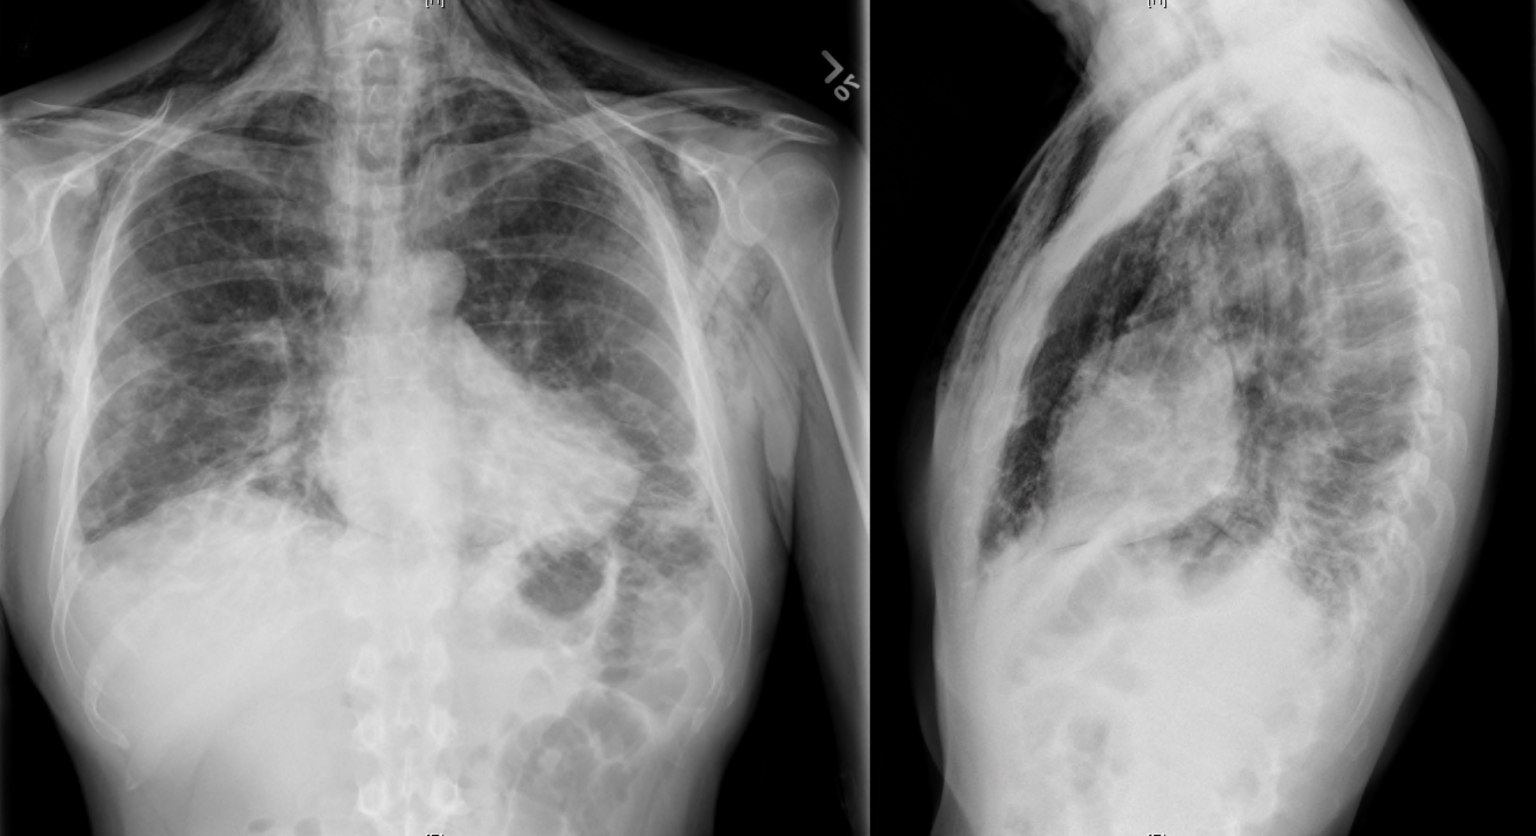

Pneumomediastinum CXR and CT Radiology at St. Vincent's University Differential Diagnosis Of Pneumomediastinum A rim of air consistent with a pneumomediastinum may be observed along the upper left border of the heart. The goals of this study were to assess the etiology of pneumomediastinum in a large cohort of trauma and nontrauma patients, identify factors predictive of esophageal and. Spontaneous pneumomediastinum results from the rupture of terminal alveoli with subsequent tracking of gas. Differential Diagnosis Of Pneumomediastinum.

Pneumomediastinum case examples. A, Patient 5 with pneumomediastinum Differential Diagnosis Of Pneumomediastinum The most important aspect of care is often treating this underlying. Most cases are benign, but a minority of cases require additional testing and intervention. Have lower threshold for additional testing. A rim of air consistent with a pneumomediastinum may be observed along the upper left border of the heart. The goals of this study were to assess the etiology. Differential Diagnosis Of Pneumomediastinum.